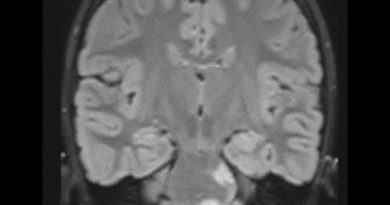

12 yaş, E

Dirençli baş ağrısı

Retroklival, Prepontin, İntradural, Saplı benign Kitle Ecchordosis physaliphora

Ecchordosis physaliphora

Ecchordosis physaliphora

Ecchordosis physaliphora